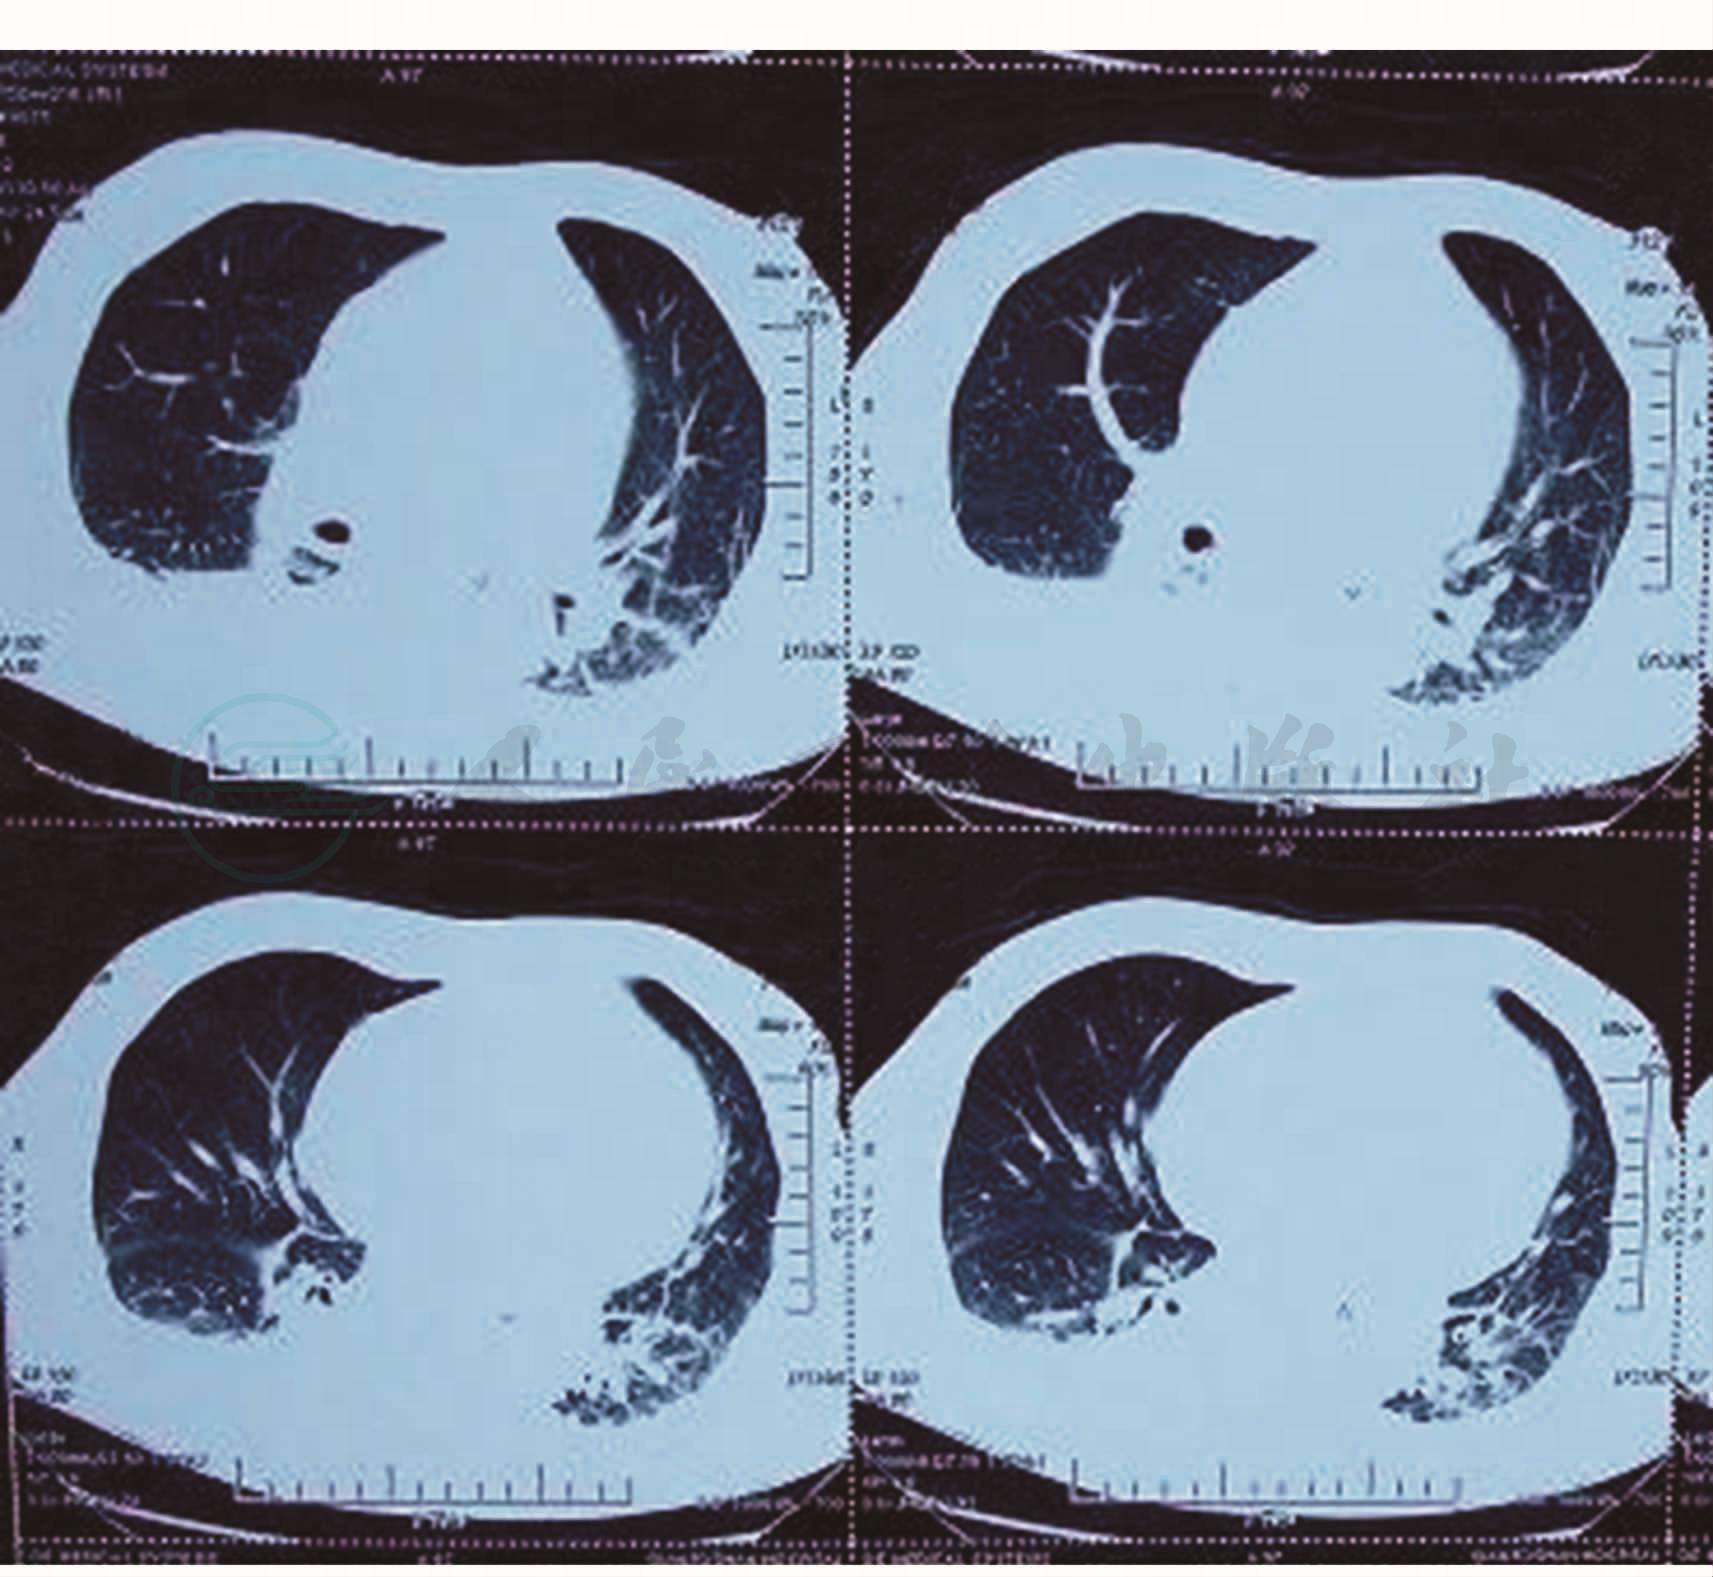

诊疗经过:入院后,完善辅助检查,血常规示WBC 6.72×109/L,N 80.7%;肝肾功能正常,行“多西紫杉醇+顺铂”化疗,入院第5天(2009年1月25日),患者自服过量“多塞平”,导致呼吸、心搏骤停,转入ICU给予气管插管呼吸机辅助通气(呼吸机通气模式SIMV)、锁骨下静脉穿刺、持续导尿及硫酸依替米星0.3g,每天1次,静脉滴注及肠内营养对症治疗6天,患者生命体征稳定,但出现持续发热,最高体温39.2℃。2009年1月31日,血常规示WBC 3.19×109/L,N 68.1%;肝功示ALT、AST正常,Alb 28.7g/L。为进一步治疗,于2009年2月1日转入本科继续治疗。当时查体:T 38.5℃,神志清,精神差,反应迟钝,双肺呼吸音粗,双下肺可闻及湿性啰音,腹股沟可触及多个肿大淋巴结,最大者1.0cm×0.5cm,余未见明显异常。无体液培养结果,经验选择亚胺培南0.5g,每8小时一次,静脉滴注抗感染治疗。2009年2月3日,尿液培养回报:奇异变形杆菌,对亚胺培南敏感。2009年2月5日,患者仍发热,体温在38℃以上,给予盐酸万古霉素0.5g,每8小时一次,静脉滴注,联合亚胺培南抗感染治疗;2009年2月6日,尿液培养回报:奇异变形杆菌,对亚胺培南敏感;2009年2月8日,2次痰培养回报:金黄色葡萄球菌(MRSA),对万古霉素、替考拉宁、利奈唑胺敏感。2009年2月10日,患者体温无下降,停用亚胺培南。后患者仍持续发热,体温在38℃以上。2009年2月14日,停用盐酸万古霉素,更换为利奈唑胺600mg,每天2次,静脉滴注治疗。2009年2月15日,痰培养回报:光滑球拟酵母菌,对氟胞嘧啶敏感,氟康唑、伊曲康唑、伏立康唑均耐药。患者仍发热,体温在39℃以上。2009年2月18日,加用卡泊芬净50mg,每天1次,静脉滴注抗真菌治疗;2010年2月19日,行胸部CT检查示双肺下叶炎症,双侧胸腔积液(图1,图2)。2009年2月21日,患者仍发热,体温无下降。于2009年2月21日行支气管镜保护性毛刷采样培养,24日回报:嗜麦芽窄食单胞菌,对头孢哌酮/舒巴坦、左氧氟沙星敏感。

图1 胸部CT(肺窗)示双肺下叶炎症、双侧胸腔积液

图2 胸部CT(纵隔窗)示:右下肺膨胀不良及双侧胸腔积液